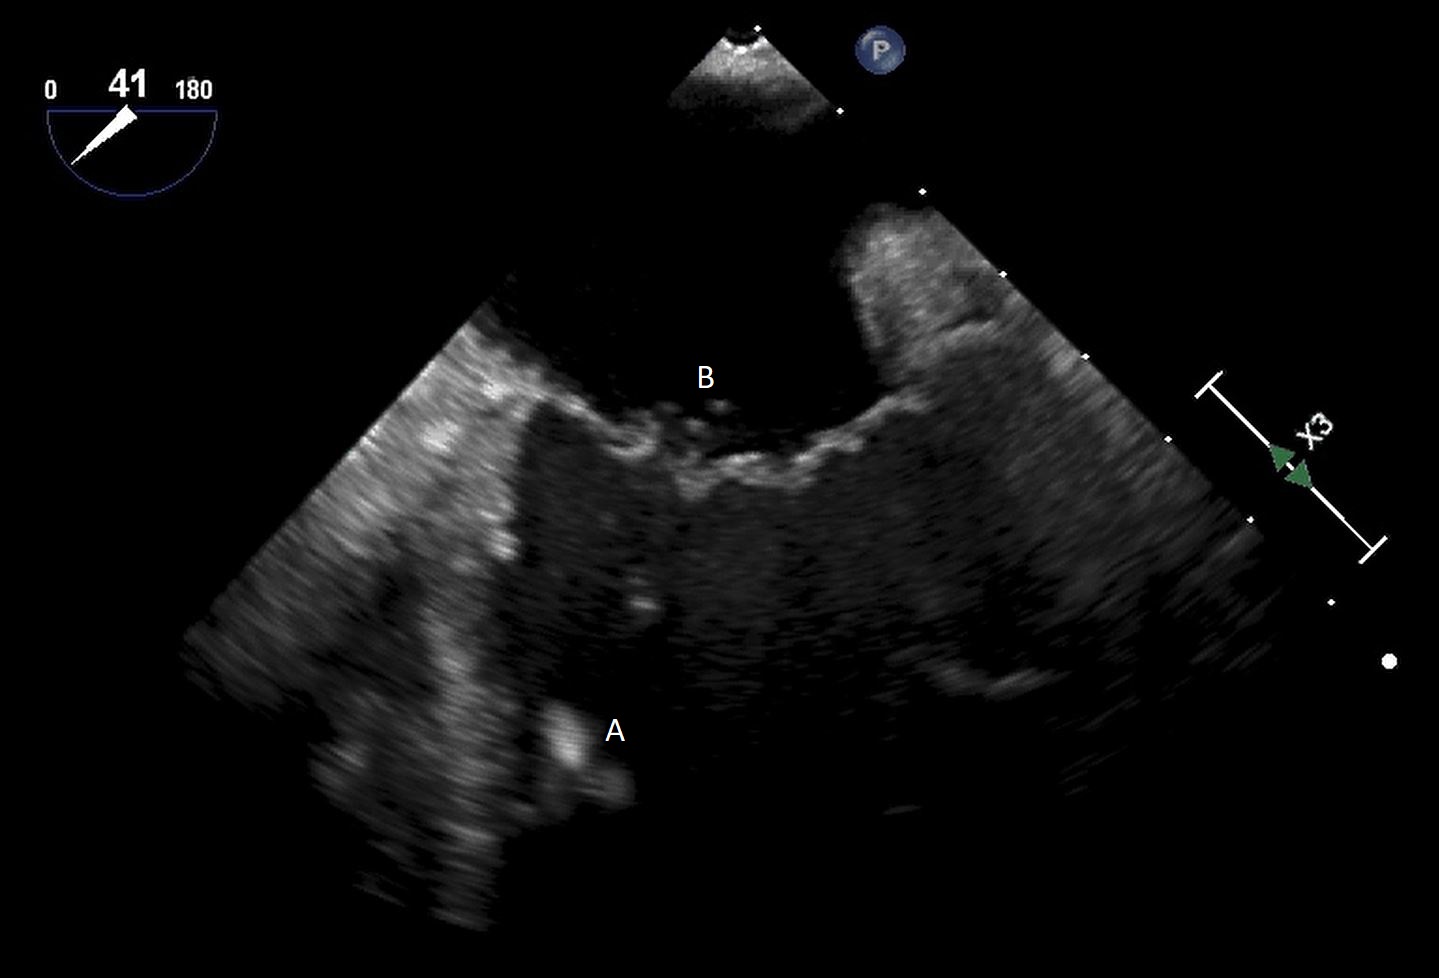

After initial access is obtained with a guidewire, TEE can confirm placement of the guidewire within the aorta and ensure there is no iatrogenic dissection from the procedure. The midesophageal long axis and 4 chamber views can be used to visualize the guidewire crossing of the aortic valve and positioning within the LV cavity. The wire tip should point towards the LV apex. Wire placement too deep within the LV can trigger ventricular arrhythmias and tethering of the mitral valve or subvalvular apparatus should be avoided as this can result in the inlet abutting the mitral valve or damage to subvalvular apparatus (Figs. 3,4) [13]. When the proceduralist is advancing the Impella over the guidewire, the best view to observe the device crossing the aortic valve is the midesophageal long axis view [13].

Impella (A) in the LV cavity caused disruption and damage to subvalvular apparatus resulting in flail segment (B) of the mitral valve.

Fig. 4.Impella (A) placement causing disruption and damage to subvalvular apparatus resulting in mitral valve flail (B) and mitral regurgitation (C).